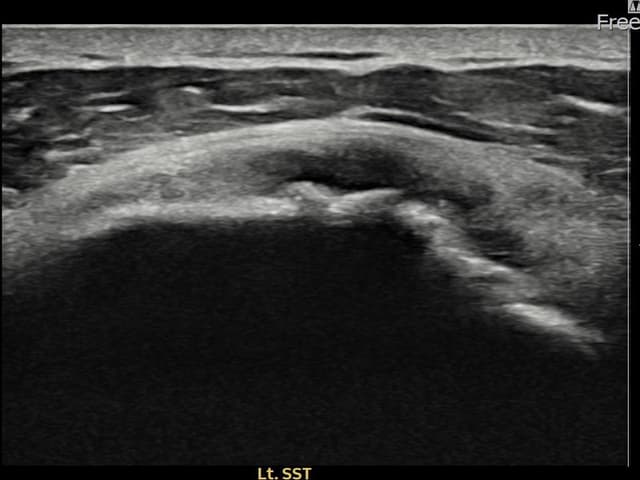

[経過期間: 23.07.18~23.09.14]

[縫縮術] 超音波検査にて左 棘上筋腱 광범위 部分断裂(15mm × 6mm (腱厚の約70%欠損))を確認。縫縮術施行後、腱の連続性が回復し、日常生活に復帰されました。